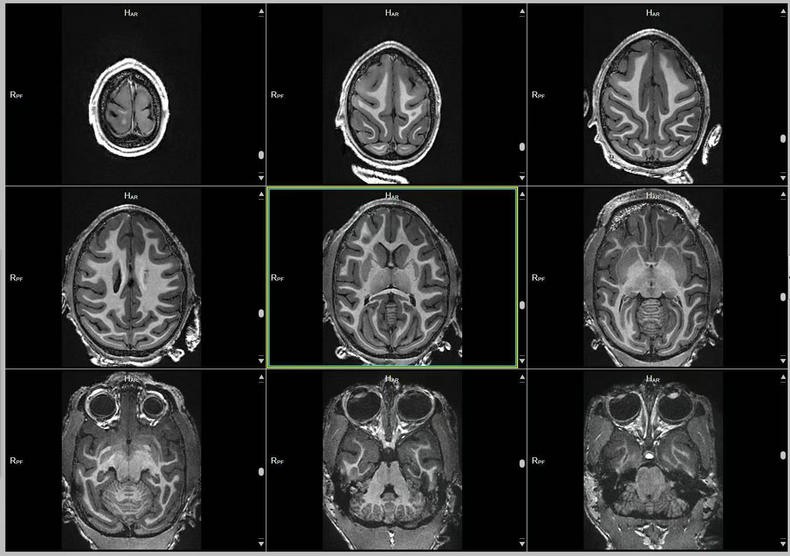

- 关键词:2023-2025年,猕猴,脑部磁共振,3D影像,T1w序列,T2w序列

预定本数据集为 2023-2025 年对 114 只 0-3 岁幼年健康雌性猕猴的脑部磁共振扫描收集的数据,主要包括 T1w 序列和 T2w 序列影像(3D 影像),对于神经学、心理学、行为学等多个相关学科的研究提供丰富的脑数据支撑。

a.物种:猕猴

b.实验动物信息

样本数量:114只

年龄分布:0-3岁

重量分布:1-6kg

性别分布:雌性114只

c.扫描仪规格

扫描仪类型:联影uMRNX 3.0T磁共振扫描仪器

线圈:12通道猕猴专用头线圈